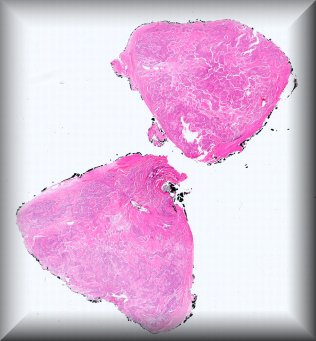

Luis Alfaro (Valencia): Rapidly growing tumour in a 51-year-old male affecting the orbit and involving the eyeball. Extended exanteration was performed, towards the skull and left facial region. Protocol |